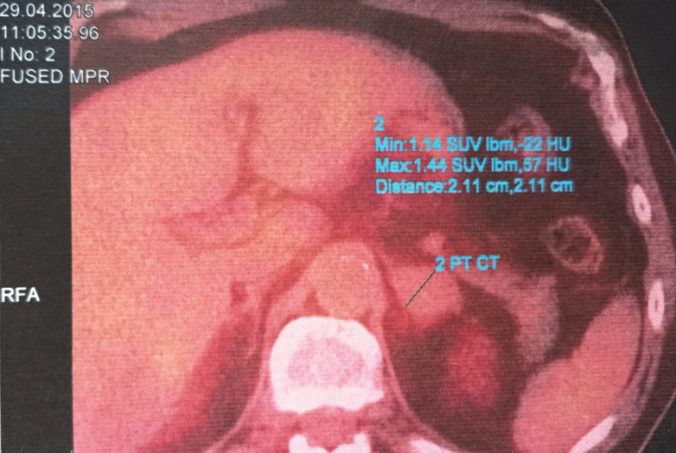

Totéž ložisko v podkoží na pravém boku dle hodnocení na PET-CT před zahájením léčby a 12 týdnů po zahájení léčby Vemurafenibem. Je patrné zmenšení ložiska a vymizení metabolické aktivity: